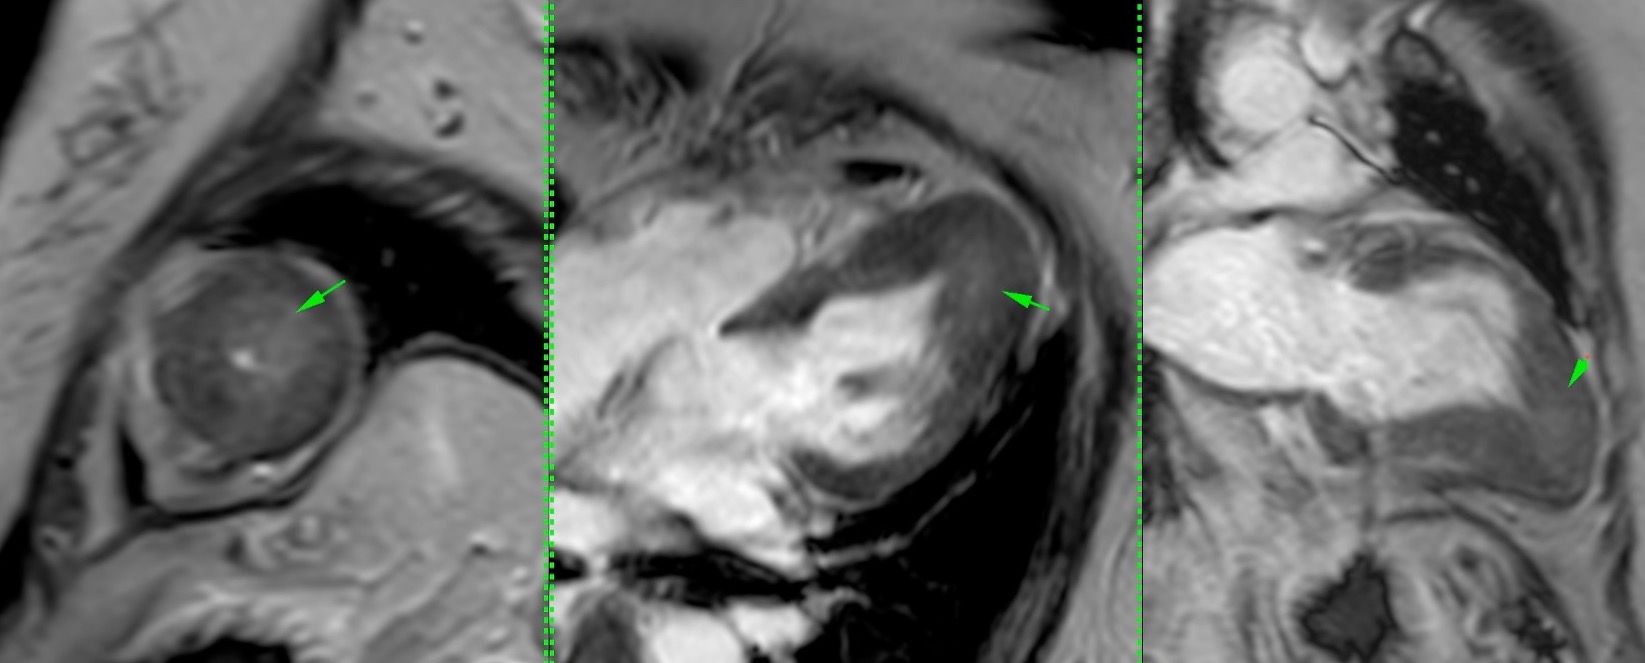

This is a 56-years old who presented with chest discomfort and echo showed apical thickening.

What do you think is the diagnosis?

- Fabry's

- Amyloidosis

- EMF

- Apical hypertrophic cardiomyopathy